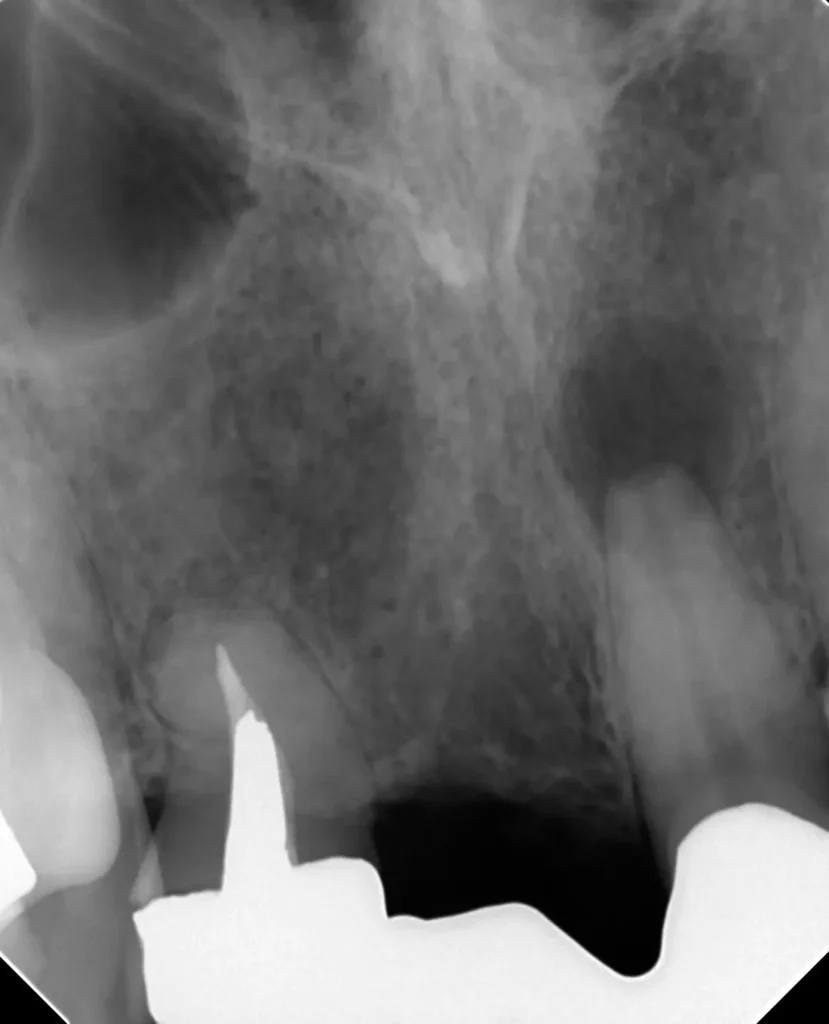

自費根管治療症例1 治療前

左上の奥歯の腫れと噛んだ時の痛みで来院。

レントゲン写真

根の先にうみが溜まっています

CT画像

副鼻腔の骨の壁を突き破っています